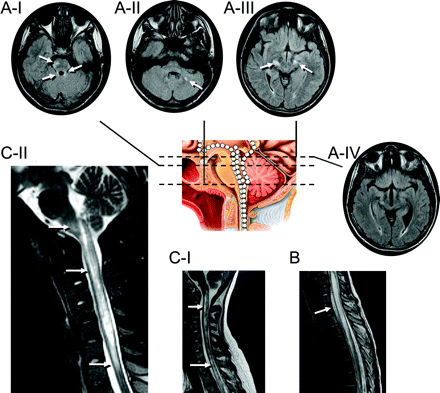

图3七个孩子代表MRI异常显示出脑干的频谱,周围,peri-IVth心室和脊髓参与地区已知高度表达aquaporin-4

白色的箭头表示异常液体衰减反转恢复或T2信号。冲黑色线条代表解剖水平关系图。(一)病人5(17岁的女孩;另请参阅图1中,E通过我)两国在上级小脑的病变总花梗(ⅰ),在小脑白质病变(A-II)和双边病变内部胶囊(A-III)。四年后病人出现症状性阻塞性脑积水(iv,也看到图1E-II;内囊损伤已经解决)。(B)病人8(11岁女孩)纵向广泛T2在中央脊髓异常通常是发现在成年neuromyelitis视(在本例中11椎段)。(我)病人9(17岁的女孩出现棘手的呕吐,四肢瘫痪,补剂肢体痉挛)和(C-II)病人11(17岁的女孩出现棘手的呕吐)纵向跨越脑干损伤和中央颈,胸线。